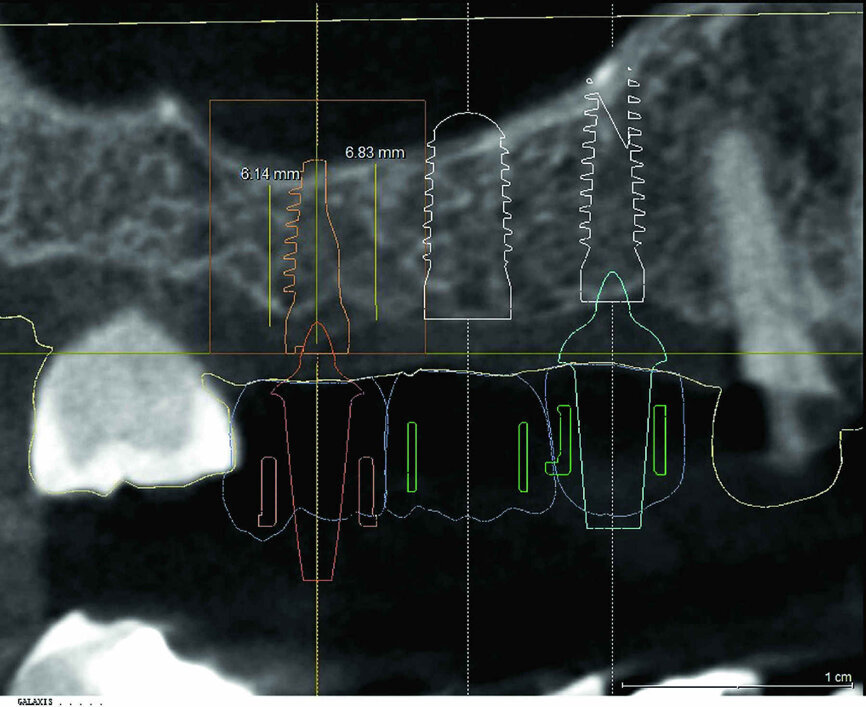

Avant le traitement chirurgical, les zones des deuxième et troisième quadrants ayant besoin d’être restaurées l’ont été au moyen d’éléments de bridge tout-céramique et dans le premier quadrant, la dent 14 a été recouverte par une couronne en disilicate de lithium produite par CAD/CAM. Une planification numérique a été utilisée pour déterminer l’orientation des implants en fonction des éléments prothétiques, afin d’obtenir la meilleure prédictibilité possible pour la réussite du traitement sur le plan clinique. Les données CBCT du scannage intraoral ont donc été superposées aux trois couronnes conçues numériquement (Fig. 3), puis les positions, les alignements axiaux et les longueurs des trois implants ont été déterminés à l’aide du logiciel de planification (Fig. 4). Étant donné qu’il n’existe encore aucune solution guidée pour le système implantaire utilisé pour ce cas, un gabarit d’orientation a été fabriqué au laboratoire d’après les données de planification rassemblées, reproduisant le bord anatomique et l’alignement des dents à remplacer. Le gabarit était précisément adapté aux dents adjacentes (Fig. 5). Implantation L’incision crestale a été réalisée après une anesthésie superficielle de la zone, suivie d’une anesthésie par infiltration. Elle a été pratiquée selon une direction légèrement palatine et s’est poursuivie par une incision paramarginale du côté vestibulaire autour de la dent 18. Aucune incision de décharge verticale localisée en distal n’a été réalisée, afin de ne pas diminuer l’apport sanguin dans les lambeaux. Après la préparation du lambeau mucopériosté, la position de l’implant a été marquée sur l’os au moyen du forêt triangulaire et du gabarit d’orientation. L’étape suivante a consisté à forer des trous de guidage jusqu’à une profondeur située légèrement sous le plancher du sinus maxillaire, car l’élévation sinusienne devait ensuite être réalisée par la technique de l’ostéotome. Les axes des trous de forage ont été vérifiés à l’aide d’indicateurs de direction et le site implantaire a été élargi selon le protocole chirurgical (Figs. 6–8).

Fig. 3 : Planification 3D : superposition des données.

Fig. 4 : Visualisation de la planification.